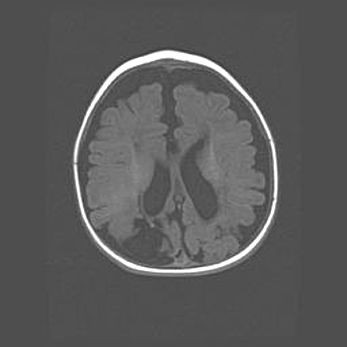

Сообщающаяся гидроцефалия. Кистозная энцефаломаляция головного мозга.

Возраст: 3 месяца 4 дня

Вес: 3100 г

Пол: женский

Окружность головы: 34 см

Срок гестации: 31 неделя

Кистозная энцефаломаляция головного мозга - одна из форм поражения головного мозга в детском возрасте. Характеризуется возникновением множественных и распространённых кист в коре, белом веществе и подкорковых образованиях головного мозга у плодов, новорождённых и детей раннего возраста. Развитие кистозной энцефаломаляции связано с внутриутробной асфиксией и гипотонией, родовой травмой, тромбозом синусов, пороками развития сосудов, инфекциями, сепсисом и другими причинами. Наиболее значимые инфекционные агенты: вирусы простого герпеса, цитомегалии, краснухи, токсоплазмы, энтеробактерии, золотистый стафилококк и другие.